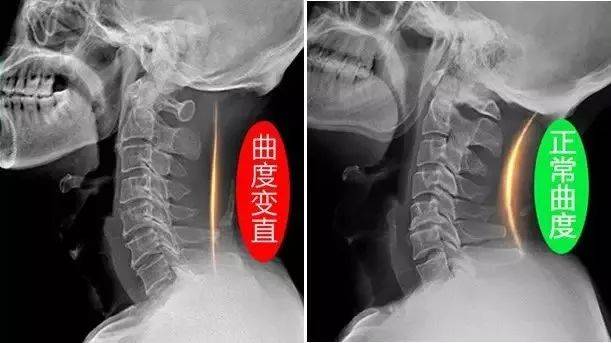

颈椎压迫神经

颈椎压迫神经相关图片